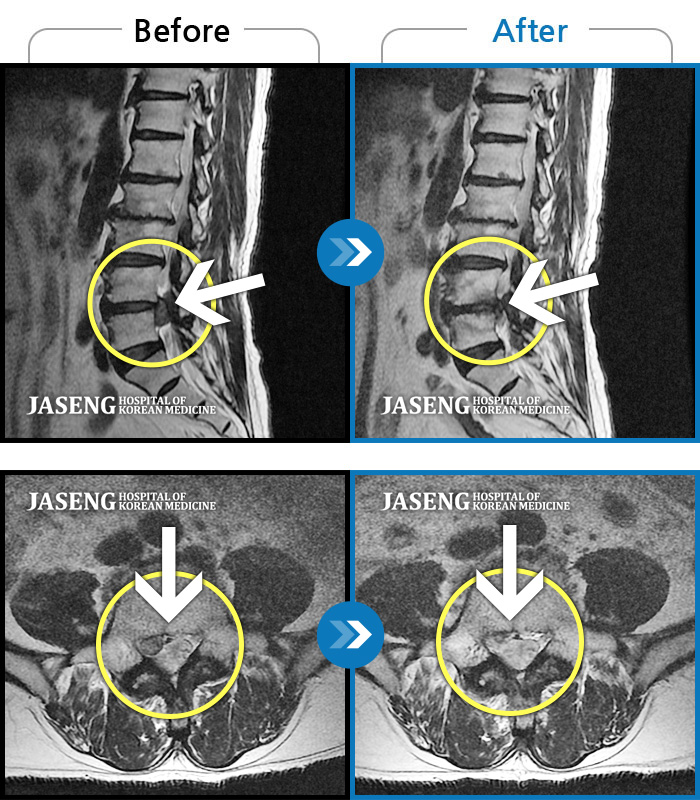

ȯںп Ǹ ǿ ԿǾ, ο ġ ۿ Ƿ ġḦ Ͻñ ٶϴ.